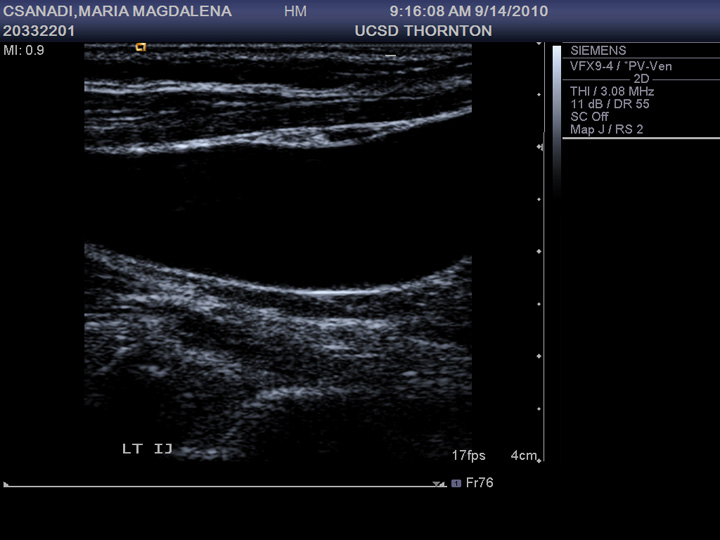

From www.pacsworlds.com

Mami’s Followup Blood Clot Ultrasound PAC's Worlds Blood Clot Ultrasound Tests used to diagnose or rule out dvt include: This article describes what to look for if you are at risk of a blood clot in the. Failure to identify and treat deep venous thrombosis can lead to devastating results, including pulmonary embolism, superior vena cava syndrome, and associated complications. Duplex ultrasonography is an imaging test that uses sound waves. Blood Clot Ultrasound.